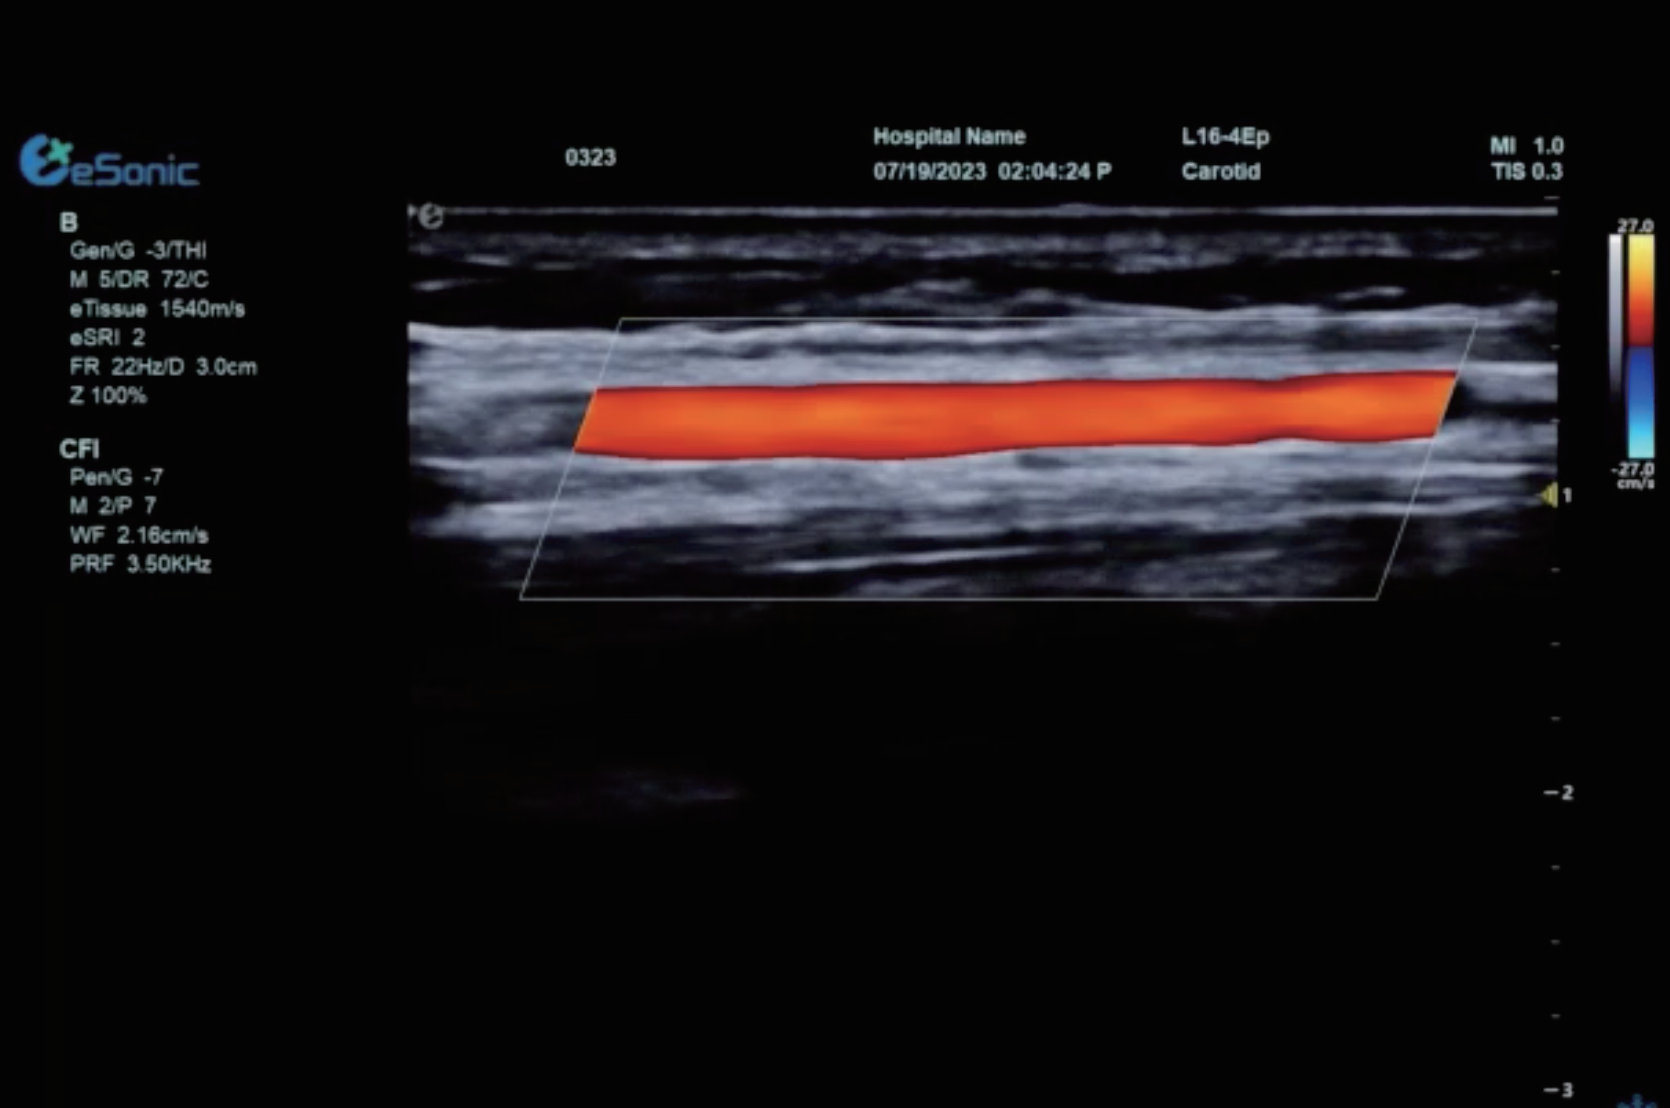

RTSWE实时剪切波弹性成像

?探头发射激励脉冲进行多点动态聚焦,利用马赫圆锥原理,形成大量的剪切波信号?颜色的变化与剪切波的速度相关,可直接体现肌肉肌腱等组织硬度值?实时、全幅、全定量

肌骨png.png

鉴别诊断、精准分级、定量评价、穿刺引导、疗效评估、随访观察